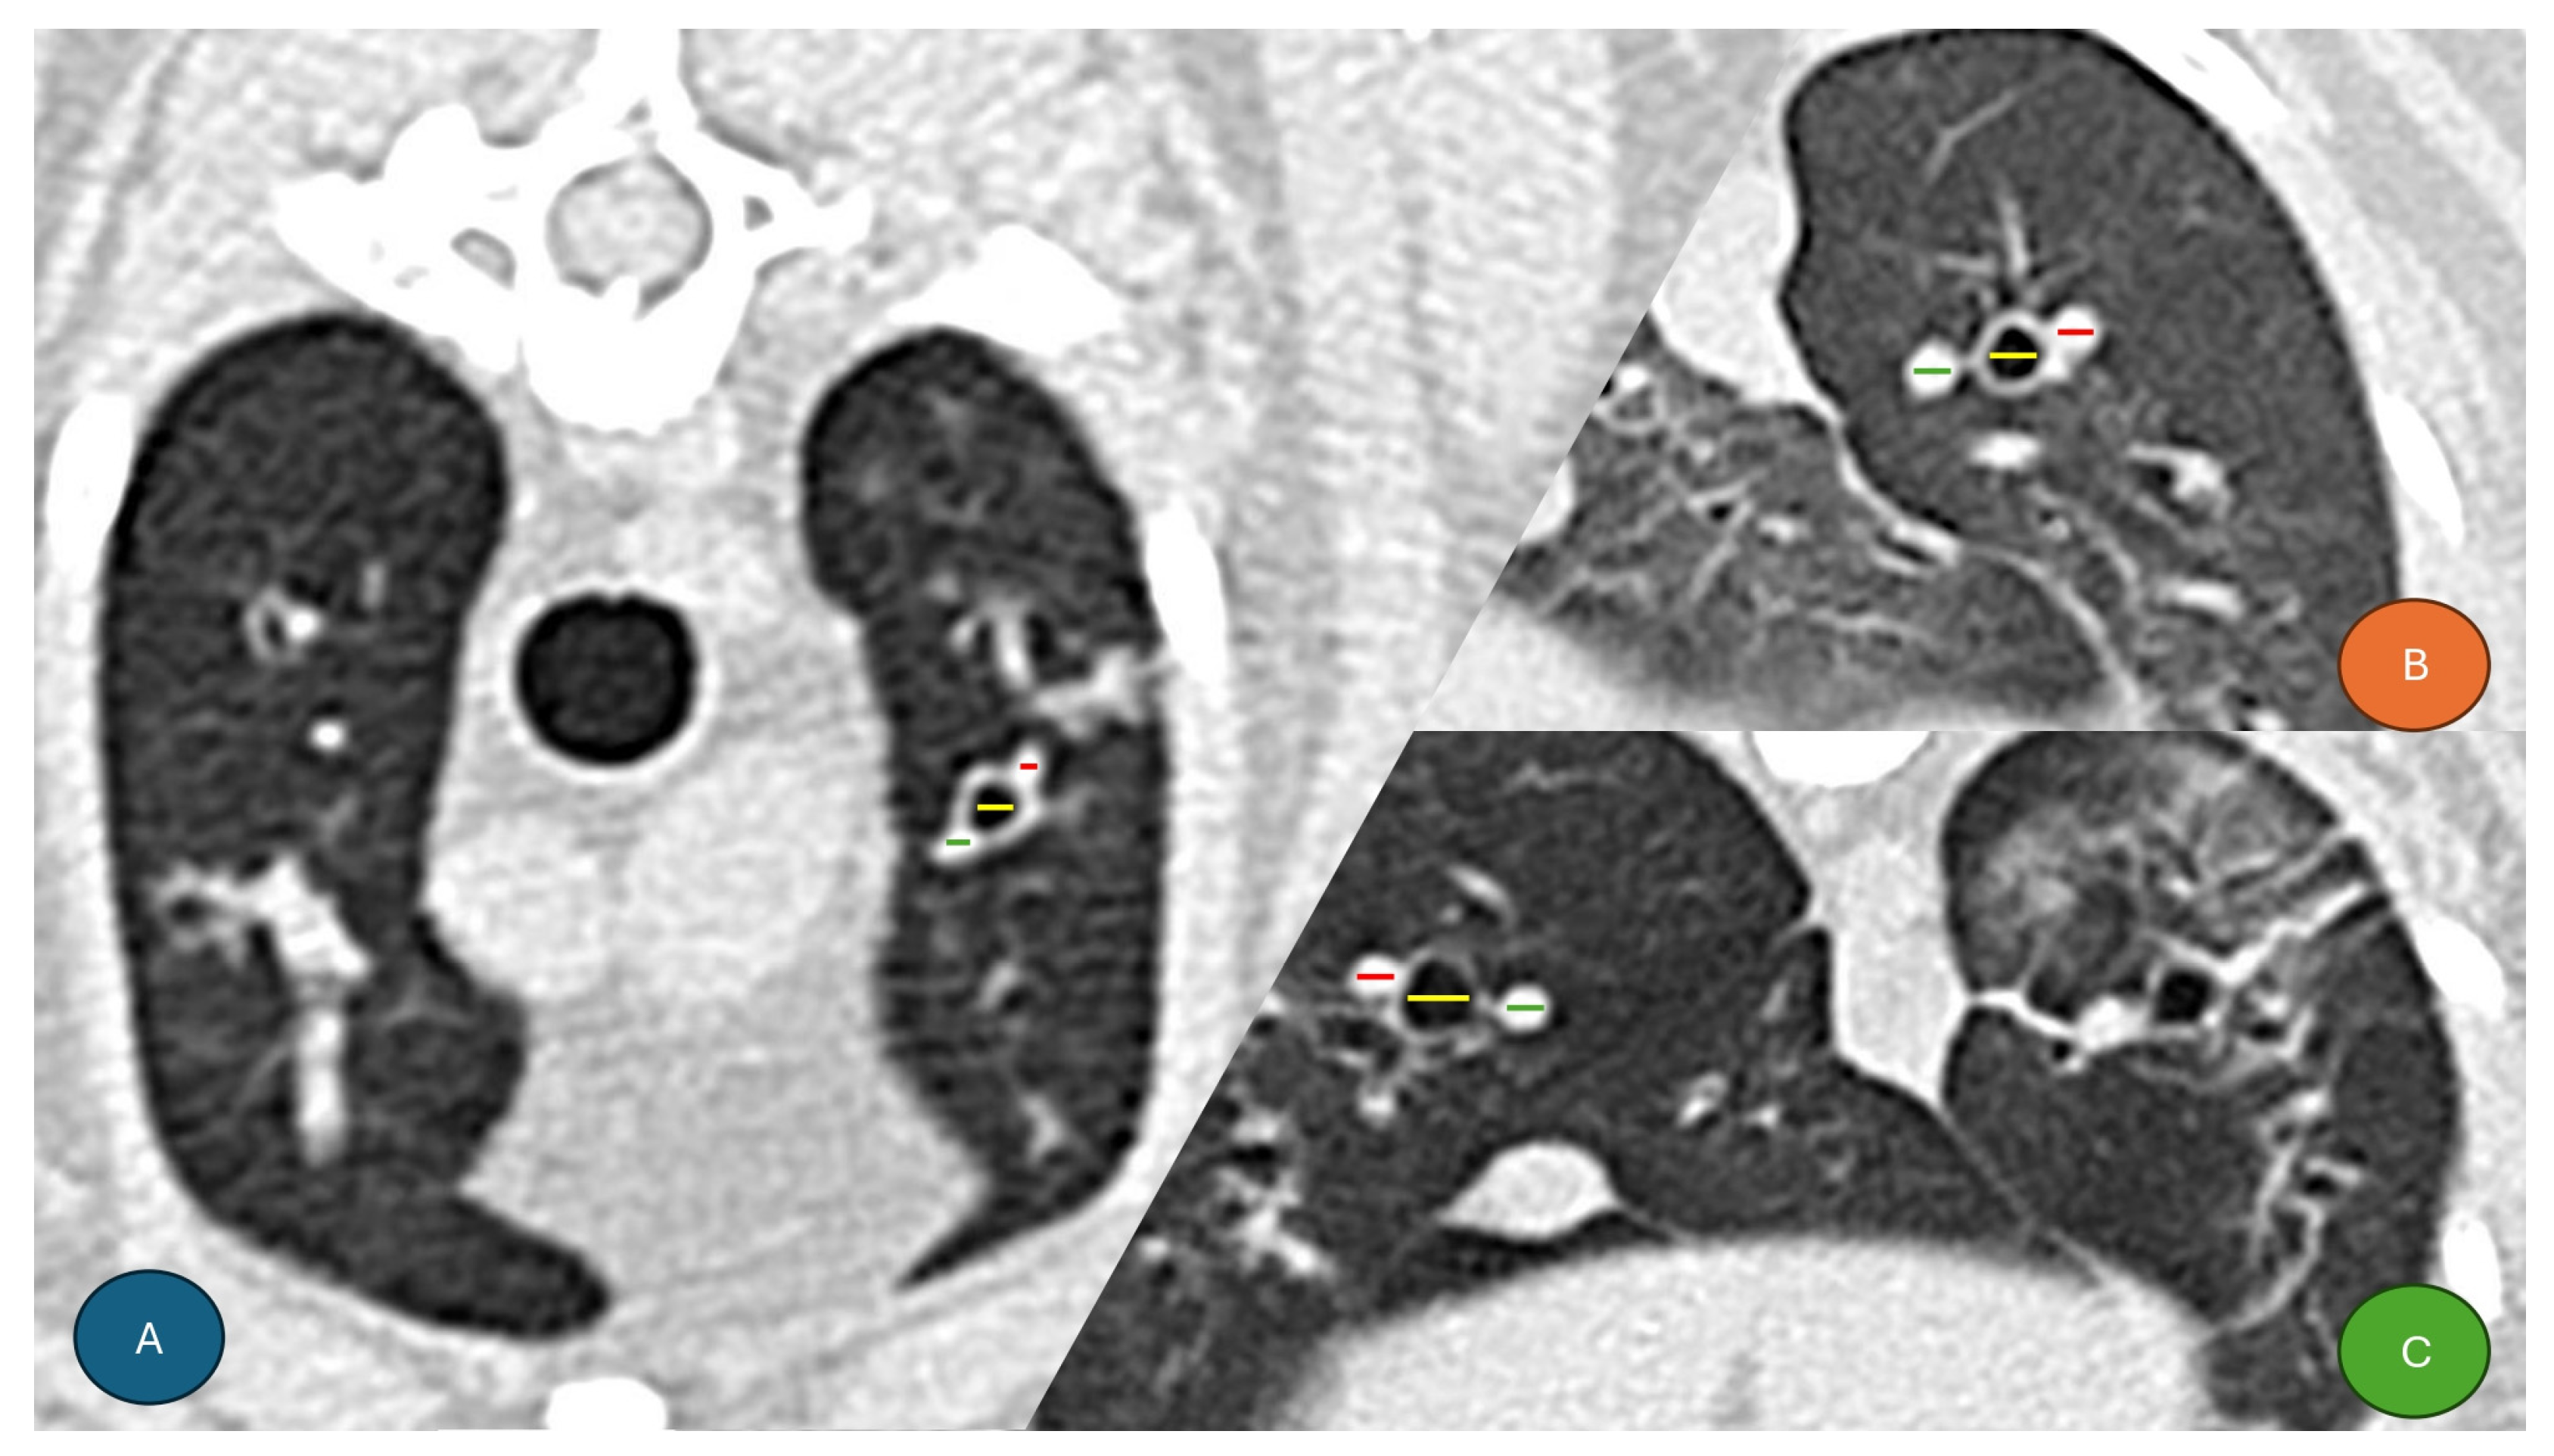

2.3. CT Scan Image Analysis

- Reid, L.; Ray Dillon, A.; Hathcock, J.; Brown, L.; Tillson, M.; Wooldridge, A. High-resolution computed tomography bronchial lumen to pulmonary artery diameter ratio in anesthetized ventilated cats with normal lungs. Vet. Radiol. Ultrasound 2012, 53, 34–37. [Google Scholar] [CrossRef]

- Lee-Fowler, T.; Cole, R.; Dillon, A.; Tillson, M.; Garbarino, R.; Barney, S. High-resolution computed tomography evaluation of the bronchial lumen to vertebral body diameter and pulmonary artery to vertebral body diameter ratios in anesthetized ventilated normal cats. J. Feline Med. Surg. 2017, 19, 1007–1012. [Google Scholar] [CrossRef] [PubMed]

- Lee-Fowler, T.; Cole, R.C.; Dillon, A.R.; Graham, S.; Tillson, D.M.; Barney, S. High-resolution CT evaluation of bronchial lumen to vertebral body, pulmonary artery to vertebral body and bronchial lumen to pulmonary artery ratios in Dirofilaria immitis-infected cats with and without selamectin administration. J. Feline Med. Surg. 2018, 20, 928–933. [Google Scholar] [CrossRef] [PubMed]